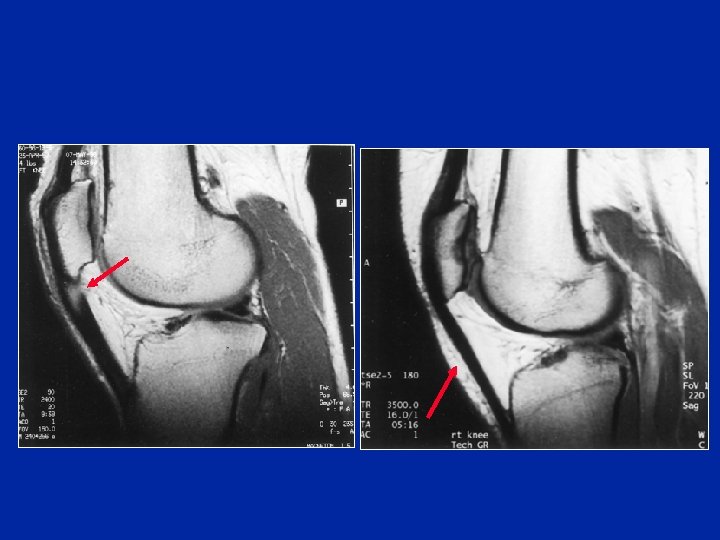

Oedème du tendon à l’IRM

Le tendon rotulien IRM Anatomie

Le tendon rotulien en IRM Documents Y. Carillon

Les examens para cliniques - La radiographie peut permettre de dépister des calcifications intra tendineuses - L'écho-tomographie permet de dépister l'existence de kystes intra tendineux - L'IRM montre la nécrose ou des nodules et parfois des calcifications

Tendinopathie rotulienne Documents Y. Carillon

Le traitement chirurgical s'adresse aux cas rebelles et aux Calcifications, nodules, micro kystes, foyers de sclérose Nettoyage du tendon. Certains associent à l'excision, le peignage du tendon. On peut aussi ajouter dans l'épaisseur du tendon malade, une greffe de tendon sain, prélevé sur un tendon voisin (patte d'oie ou tendon du quadriceps) Tendinite haute du tendon rotulien à l’IRM. Lésions à l’opération. Greffe d’une bandelette de tendon quadricipital Photos B. Moyen